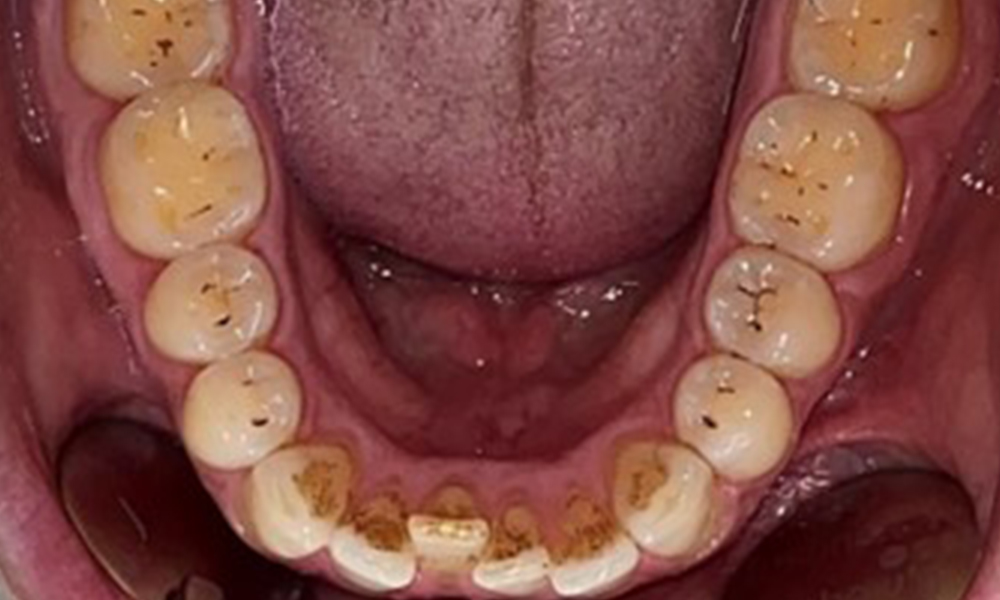

Occlusal view of the mandible, © Dr R. Krapf

Fig. 4: Occlusal view of the mandible, © Dr R. Krapf

The patient has full dentition with a total of 28 teeth. There were noteworthy erosions and attritions. (Fig. 4, Fig. 5). Due to bruxism, the patient has been wearing a splint with an adjusted bite block at night for many years. The erosions were caused by long-term consumption of isotonic beverages. No periodontal bone loss or active caries were observed.